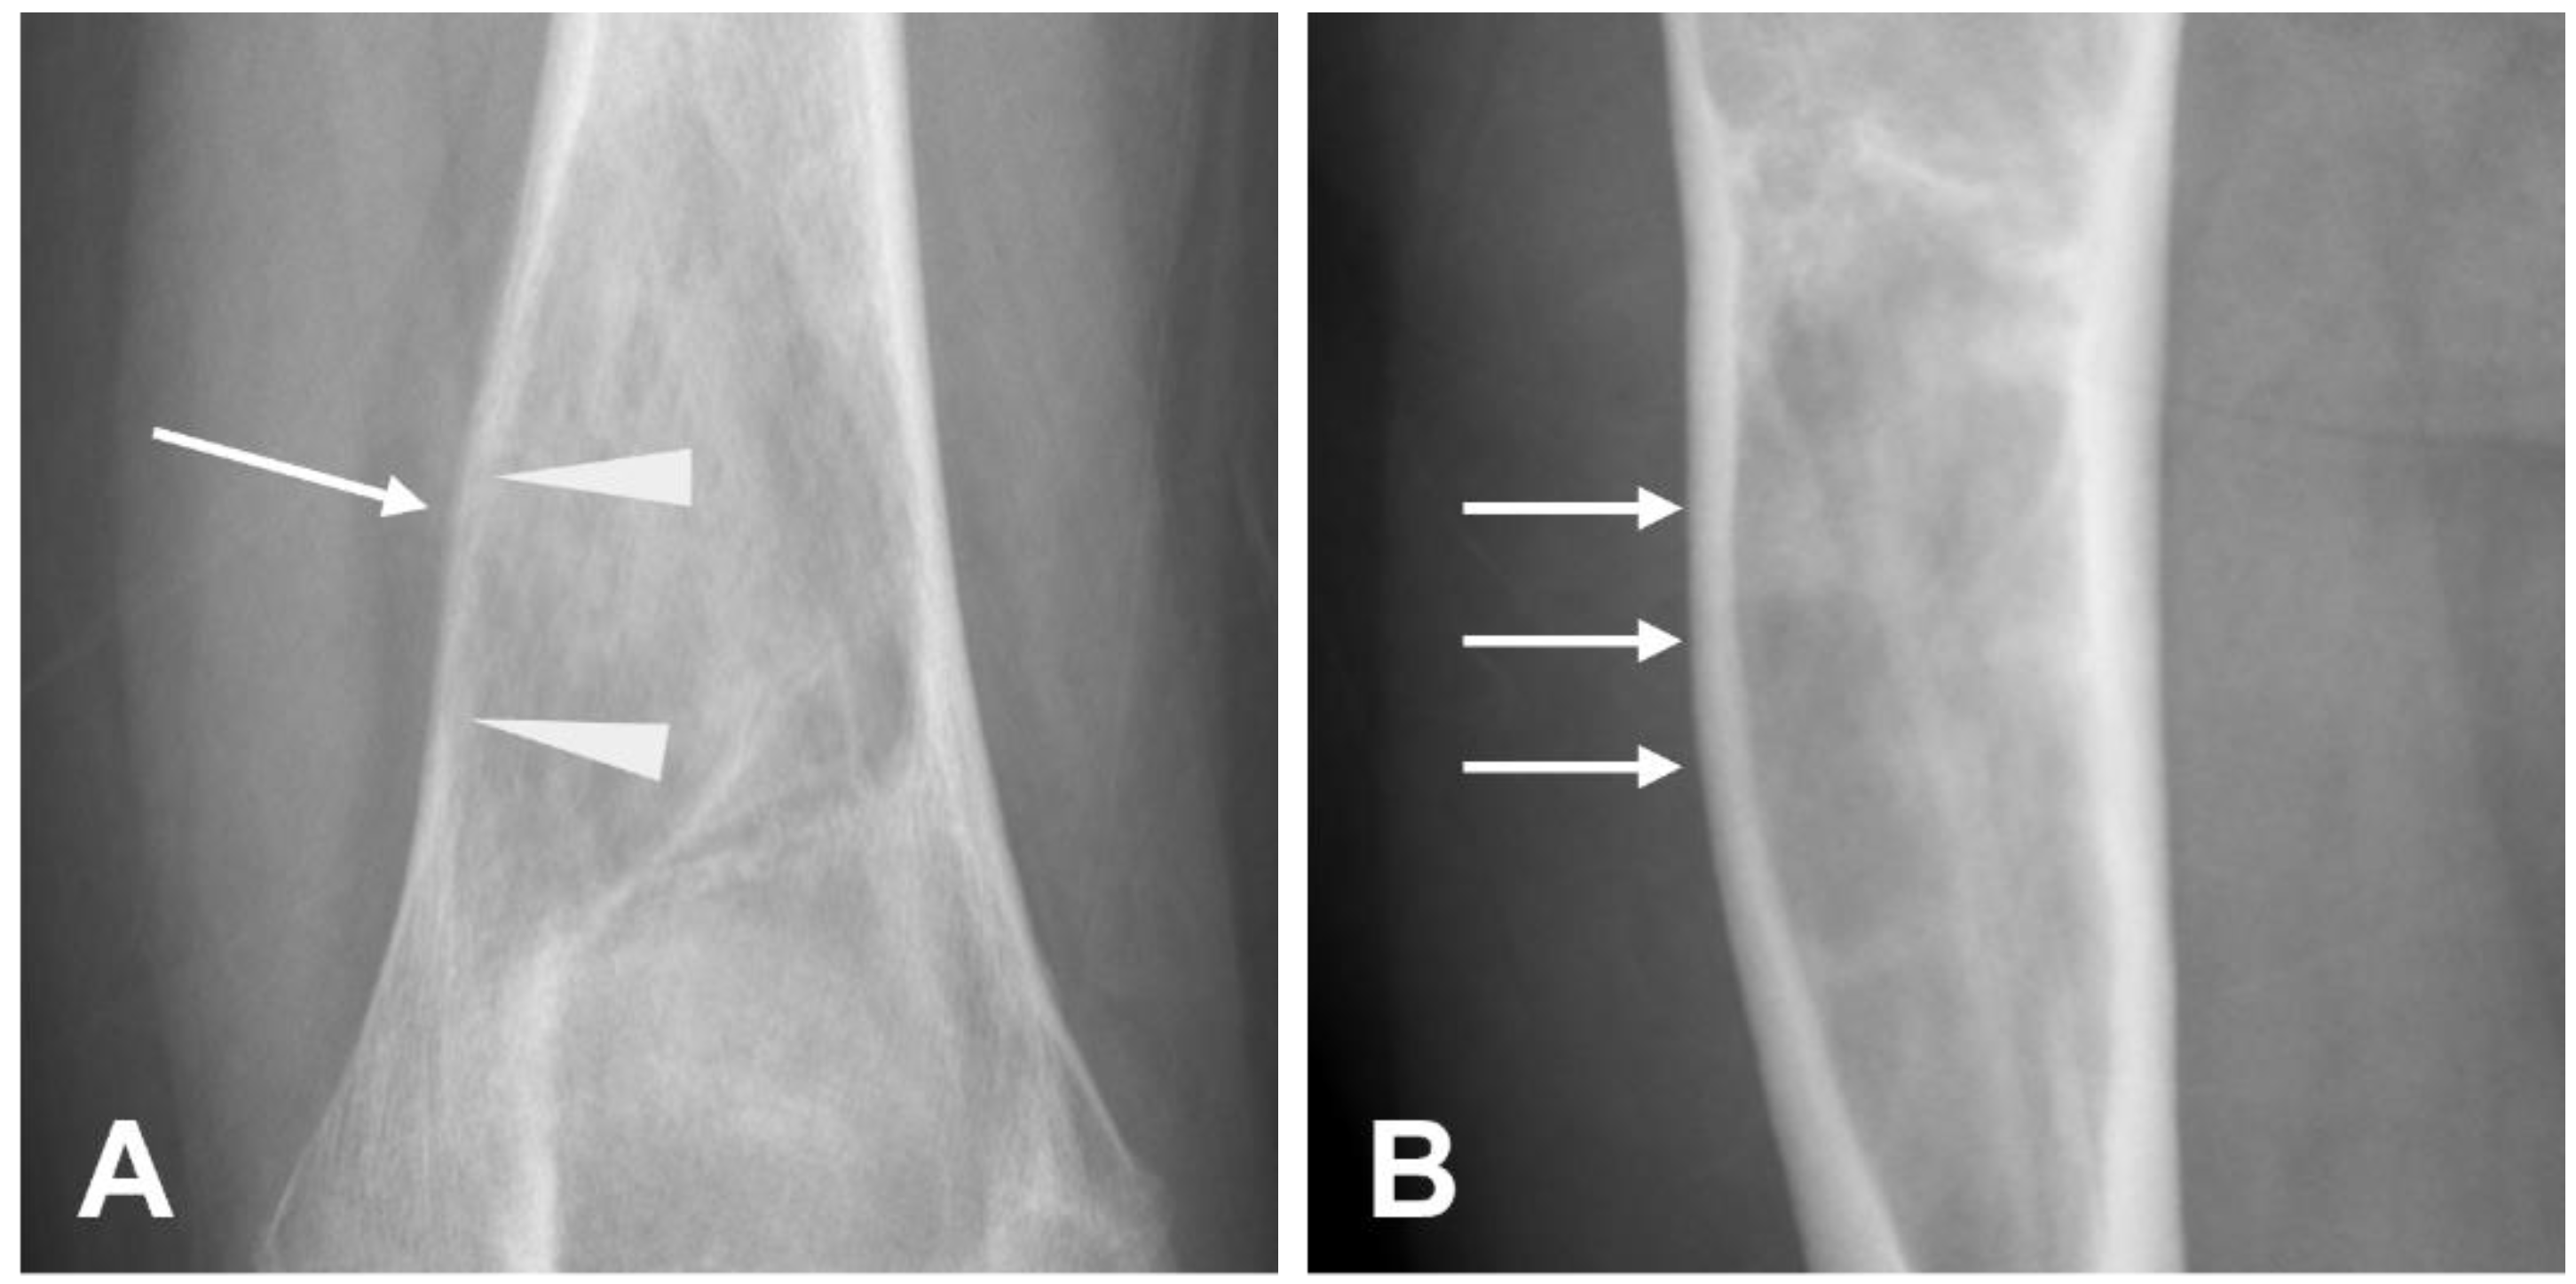

3.2.1. Parosteal Osteosarcoma

- Hang, J.-F.; Chen, P.C.-H. Parosteal Osteosarcoma. Arch. Pathol. Lab. Med. 2014, 138, 694–699. [Google Scholar] [CrossRef]

- Harper, K.; Sathiadoss, P.; Saifuddin, A.; Sheikh, A. A Review of Imaging of Surface Sarcomas of Bone. Skeletal Radiol. 2021, 50, 9–28. [Google Scholar] [CrossRef] [PubMed]

- Okada, K.; Frassica, F.J.; Sim, F.H.; Beabout, J.W.; Bond, J.R.; Unni, K.K. Parosteal Osteosarcoma. A Clinicopathological Study. J. Bone Joint Surg. 1994, 76, 366–378. [Google Scholar] [CrossRef] [PubMed]

- Campanacci, M.; Picci, P.; Gherlinzoni, F.; Guerra, A.; Bertoni, F. Neff Parosteal Osteosarcoma. J. Bone Joint Surg. Br. 1984, 66-B, 313–321. [Google Scholar] [CrossRef] [PubMed]